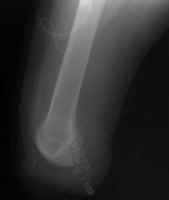

The knee disarticulation

results in an excellent weight-bearing stump. It is most often used in children and

young adults, but is nearly always avoided in the elderly and patient with ischemic

disease. Several advantages of the knee disarticulation include: 1) a

large end surface covered by skin and soft tissues that is naturally suited for weight

bearing; 2) a long lever arm controlled by strong muscles; 3)

increased stability of the patients prosthesis. A main disadvantage of the knee

disarticulation is cosmetic. The patient's prosthetic leg will have a knee that

extends far beyond his own knee in the sitting position. This tends to leave the

portion of the prosthesis below the knee dangling off the floor when the patient sits.

The image shown demonstrates an immediate post-operative knee disarticulation.